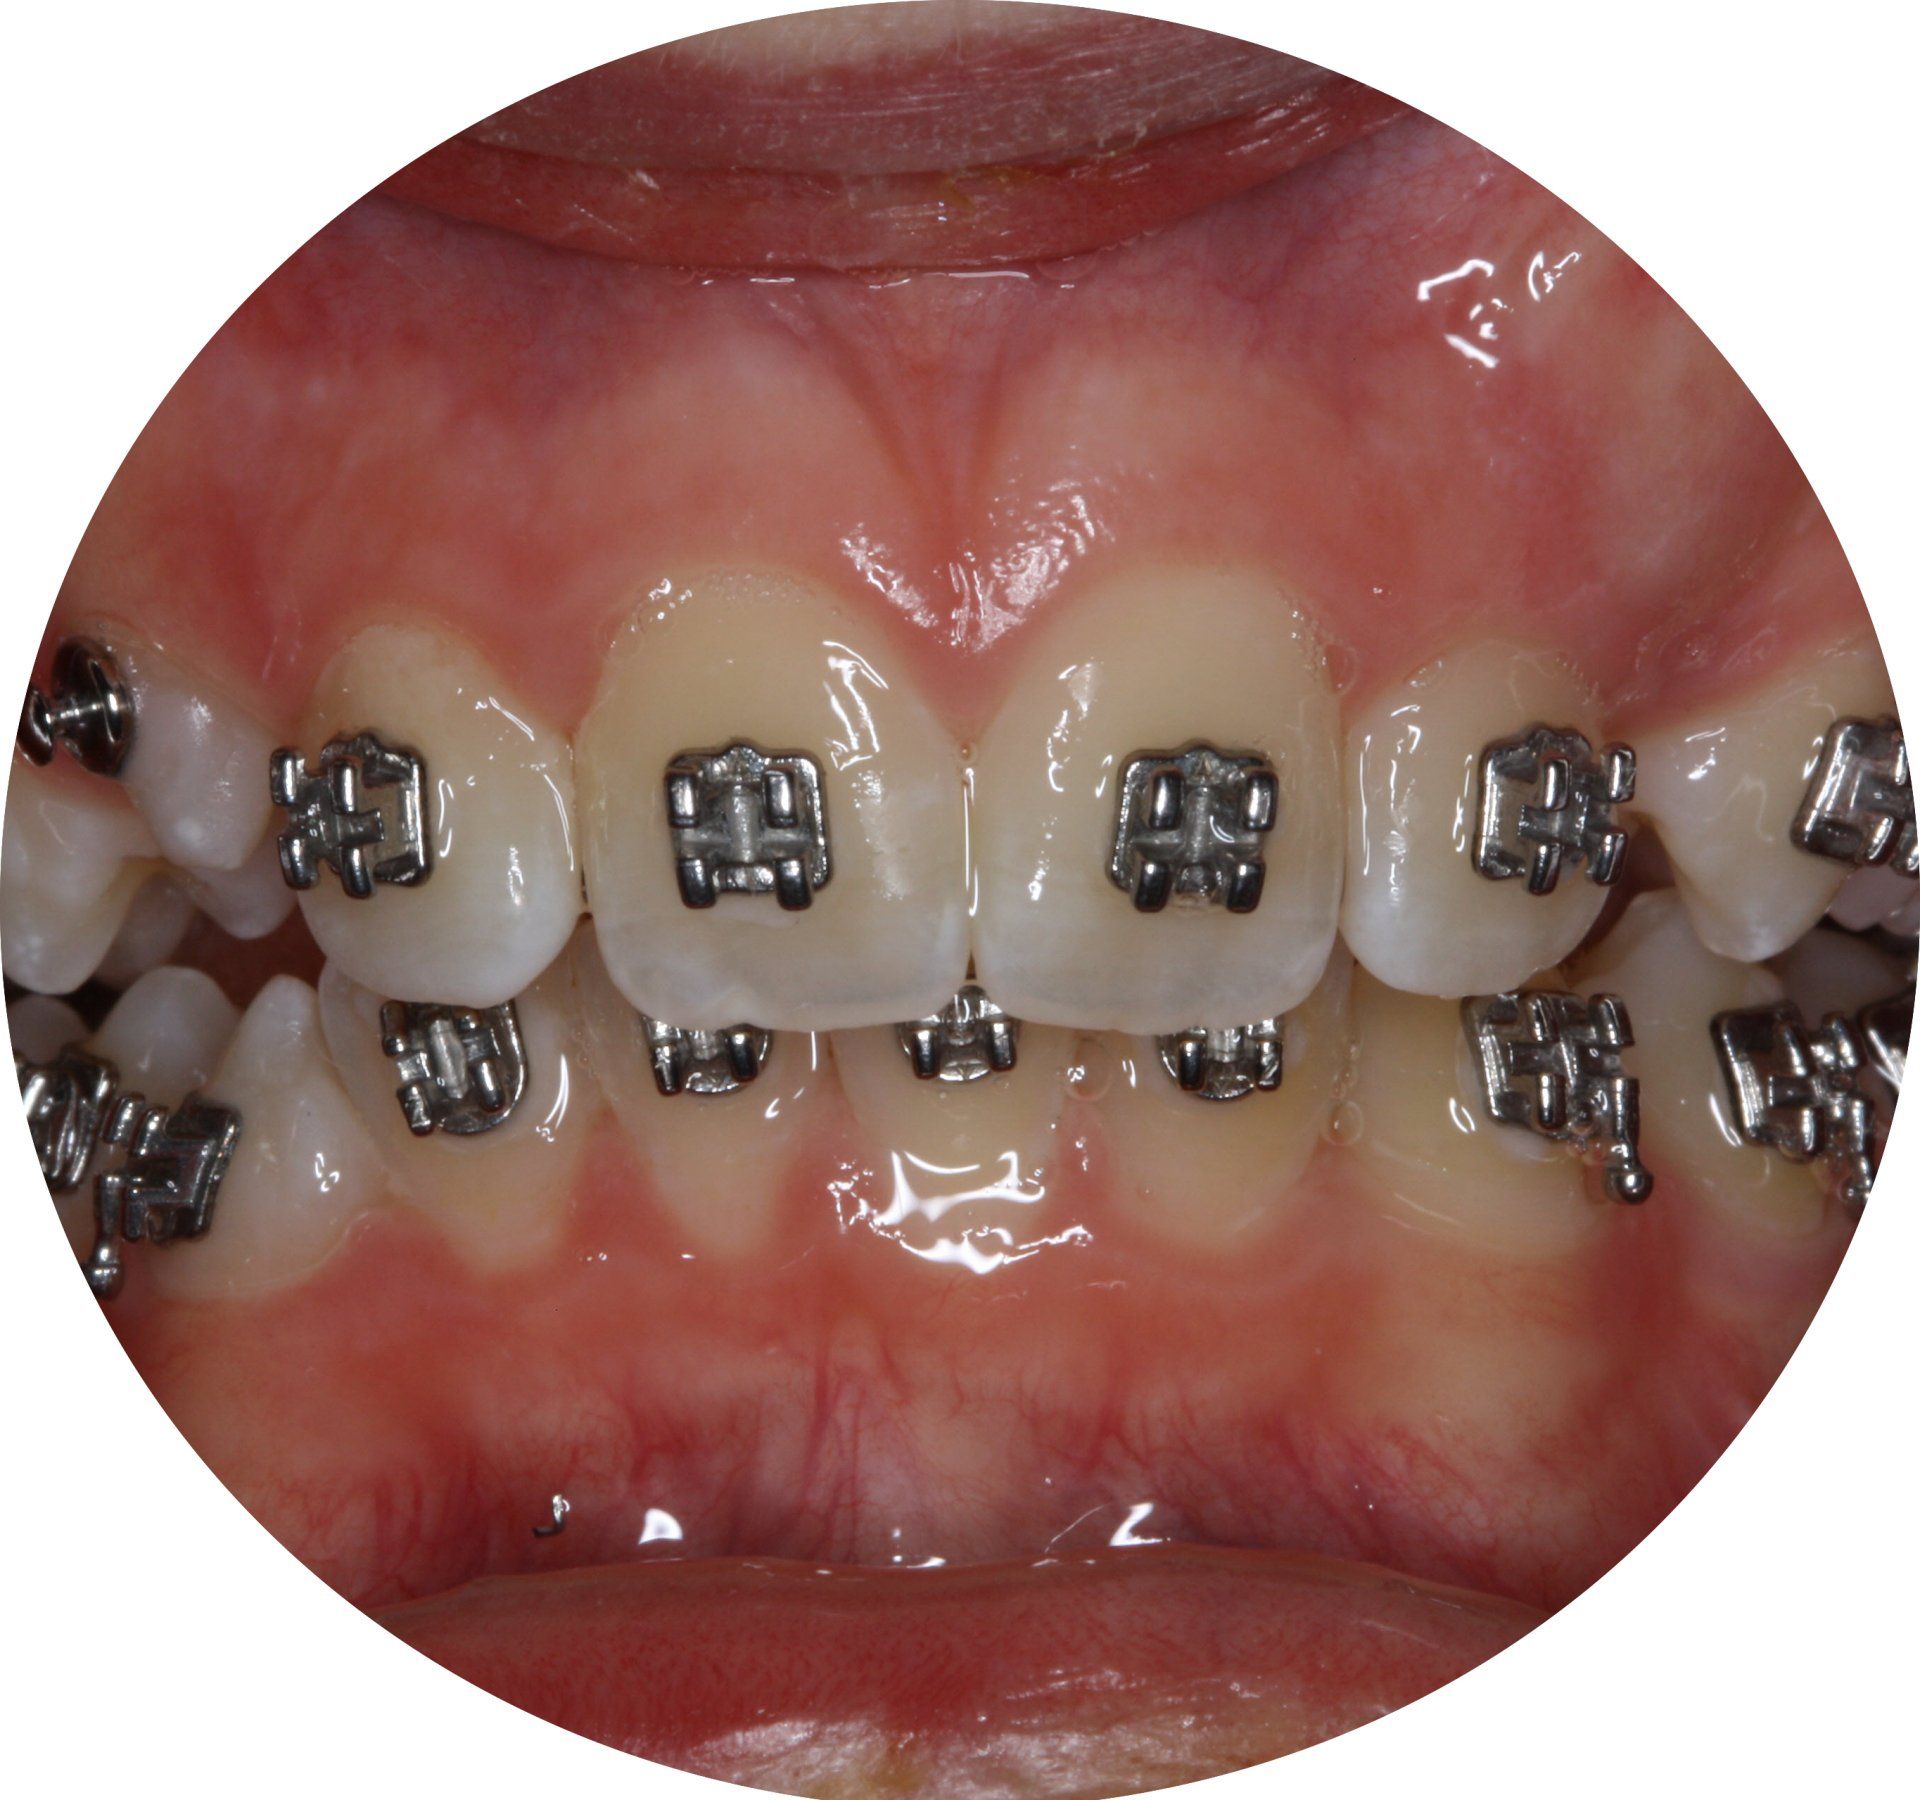

MULTIBAND THERAPIE

Bei der festsitzenden Therapie werden Hilfsteile - Brackets genannt- auf dem Zahnschmelz adhäsive befestigt, zu deutsch: geklebt.